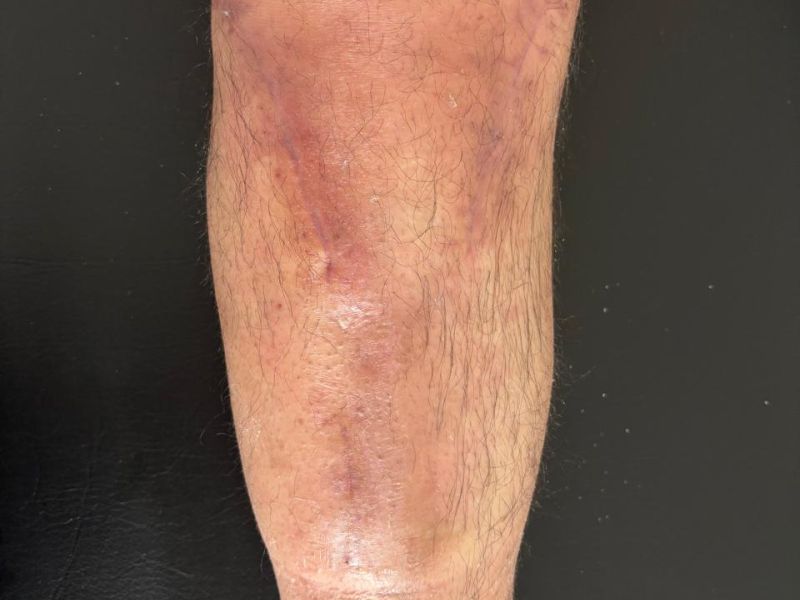

OSTEOSÍNTESIS

El POP de osteosíntesis de platillos tibiales inicia con edema, eritema, dolor y limitación funcional, propios del proceso inflamatorio postquirúrgico. La imagen de “antes” corresponde a este estado inicial, previo a recibir las sesiones de ondas diamagnéticas.

Con el manejo terapéutico se busca reducir la inflamación, mejorar la circulación y recuperar la movilidad. La imagen de “después” evidencia la evolución tras la quinta sesión, con disminución del edema y una mejoría funcional significativa.